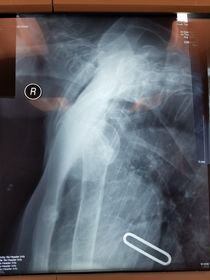

Which projection/position is this? Transthoracic Shoulder ___________________ ribs are blurred out from orthostatic breathing